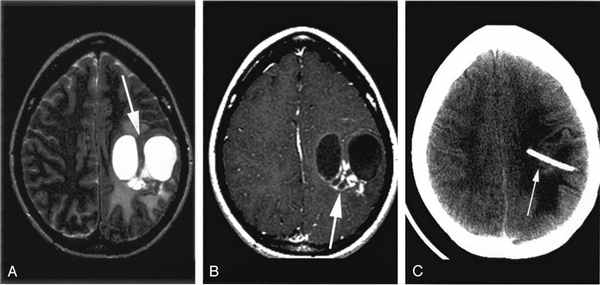

Киста шишковидной железы 9х13 мм с частичной компрессией водопровода, микроаденома до 3 мм передней доли

Обращало внимание сочетание гиперпролактинемии, микроаденом и кист шишковидной железы. Так, в настоящем исследовании, в группе практически здоровых лиц мелкие кисты (от 6 до 7 мм) отмечались в единичных случаях (до 4%), а у больных с гиперпролактинемиями в случайной выборке (n=45) кисты отмечались в 34% случаев. Еще больший процент отклонения в размерах шишковидной железы от нормы был при аденомах и при приёме контрацептивов, где максимальное значение достигало 50%. При этом размеры шишковидной железы уже составляли: передне-задний до 11 мм; высота – 6-7 мм, что значительно превышало размеры шишковидной железы в контрольной группе (p < 0,05; при t=1,14; n>30).

Вместе с тем «ингибирующий» характер увеличения шишковидной железы отмечался у больных с микроаденомами гипофиза, локализующимися как в передней, так и в промежуточной части гипофиза. Чаще всего в форме ретенционной кисты шишковидная железа была в тех случаях, когда в анамнезе были детские инфекции, риносинуситы, а также травмы и инфекции в родах. При контрастировании парамагнетиками края таких кист и иногда сами кисты хорошо накапливают контраст (рис. 3).

Из литературы известно, что шишковидная железа - это образование эллипсоидной формы, размеры которого составляют до 12 мм в длину, 3-8 мм в ширину и 4 мм в толщину, её вес равен от 0,1 до 0,18 г. Она расположена в головном мозге между верхними буграми четверохолмия и относится к органам внутренней секреции [3]. Эпифиз входит в состав промежуточного мозга и состоит из нейроглиальных и пинеальных клеток, складывающихся в тяжи и мелкие дольки. Кистозное образование диагностируется лишь у 1,5% пациентов среди всех интракраниальных новообразований [4]. Принято считать, что основной причиной формирования кист шишковидной железы головного мозга является закупорка выводящего канала, вследствие чего нарушается отток продуцируемого железой мелатонина. При закупорке выводящего протока происходит аккумуляция секрета. Другая причина - это паразитарные инвазии, провоцирующие образование паразитарных кист в различных органах. Случайная находка кисты шишковидной железы встречается в 25% случаях при жизни (при бессимптомном течении), однако на аутопсии они обнаруживаются в 40% случаев [5]. Размеры кист широко варьируют от 1-2 до 20 мм. В наших случаях кисты чаще встречались у женщин, по данным литературы, это соотношение составляет 3:1, средний возраст пациентов с данной патологией 27 лет [6]. Клинические проявления кист эпифиза весьма разнообразны: выраженные головные боли, признаки гидроцефалии, компрессии мозжечка, а также синдром Парино, к менее грозным, но не менее значимым признакам относятся: двоение в глазах, ухудшение зрения, депрессия, нервозность, прибавка массы тела, нарушение менструального цикла, бесплодие [7]. Клиническое ведение пациентов с кистами шишковидной железы остается спорным, особенно для пациентов с неспецифическими симптомами [8].